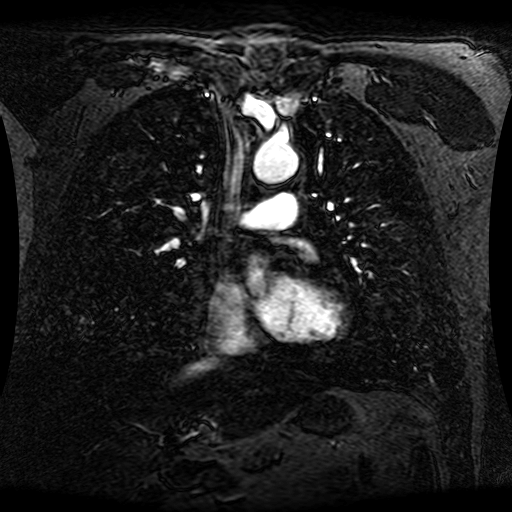

These magnetic resonance angiography (MRA) images show coronal slices acquired from consecutive anteroposterior positions within the torso. The study was performed on a 1.5T General Electric (GE) Signa imaging system with gadolinium-contrast-enhancement for visualization of the cardiopulmonary vasculature. The pulse sequence used was a 3D time-of-flight fast spoiled gradient recalled acquisition in steady state (FSPGR, TR=6.3, TE=1.4, NEX=1, FOV = 40cm, slice thickness = 1.2mm).

This sample image contains 76 frames. It is available in DICOM format (E1154S7I.dcm), as an animated GIF (E1154S7I.gif), as .ogg, .mp4, .webm, and .swf animations (one of which is shown above), or as individual PNG-format frames (see below).